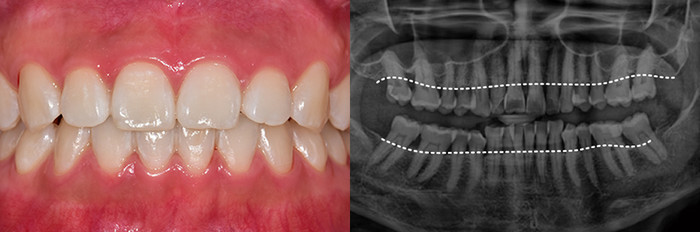

치주질환을 방치하면 뼈가 녹아내리며, 결국 발치에 이르게 됩니다. 잇몸이 무너진 후 치료는 더욱 어렵습니다.

잇몸이 붉지 않고, 연분홍빛을 띠며 단단하게 치아를 감싸고 있습니다. 엑스레이 에서는 치아 뿌리를 따라 잇몸뼈가 치아 경계선 바로 아래까지 촘촘하게 유지되 고 있습니다.

치주질환 그대로 방치한다면

잇몸뼈까지 소실됩니다

치주질환을 방치하면 뼈가 녹아내리며, 결국 발치에 이르게 됩니다.

잇몸이 무너진 후 치료는 더욱 어렵습니다.

잇몸이 붉지 않고, 연분홍빛을 띠며 단단하게 치아를 감싸고 있습니다. 엑스레이에서는 치아 뿌리를 따라 잇몸뼈가 치아 경계선 바로 아래까지 촘촘하게 유지되고 있습니다.